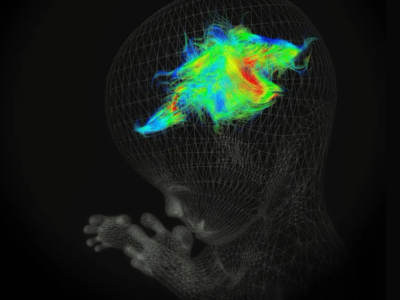

No 1 | Planifier la résection d’une tumeur cérébrale à l’aide des circuits cérébraux